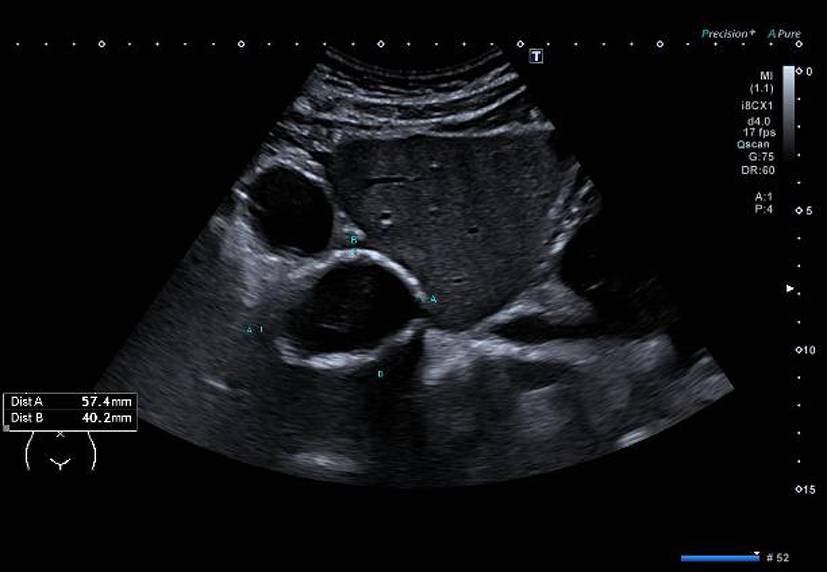

Die alveoläre Echinokokkose (AE) zeigt in der Bildgebung eine breite morphologische Variabilität und kann sowohl zystische als auch solide oder gemischt zystisch-solide Strukturen aufweisen (Abb. 1). Selbst für erfahrene Radiologen ist es oft schwierig, AE-Läsionen von malignen Erkrankungen wie intrahepatischem Cholangiokarzinom oder Lebermetastasen sowie von benignen Veränderungen wie Hämangiomen oder zystischer Echinokokkose zu unterscheiden. Zur Klassifizierung von AE-Läsionen wurden für Ultraschall, CT und MRT verschiedene deskriptive Systeme entwickelt [1315]. Diese haben aktuell vor allem in der Forschung eine Bedeutung. Im Ultraschall erscheint eine AE häufig als avaskulärer, gemischt echogener Tumor mit pseudozystischen oder verkalkten Anteilen, was gelegentlich Hämangiomen oder Metastasen ähneln kann [15]. Ein wichtiger Aspekt in der Bildgebung ist, dass der Nachweis von Verkalkungen nicht als Zeichen einer inaktiven Erkrankung gewertet werden darf [16].

Abb. 1

Verschiedene Präsentationen der alveolären Echinokokkose im Ultraschall. a AE, metastasenähnlich, b AE, hämangiomähnlich, c AE, primär zystisch, d AE, primär solide